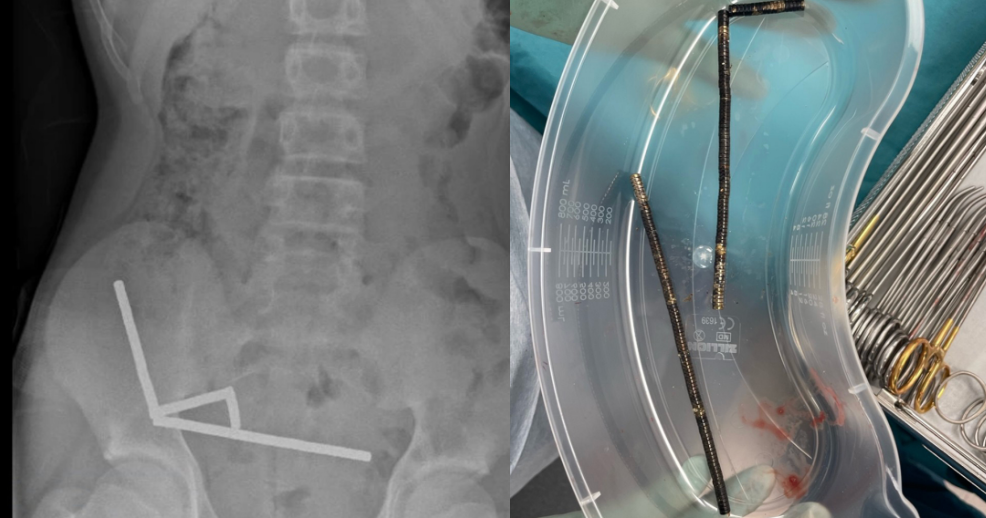

Teen in New Zealand Undergoes Surgery to Remove Up to 200 Swallowed Magnets

A 13-year-old boy in New Zealand swallowed up to 100 high-power magnets bought online, leading to surgery to remove necrotic tissue from his intestines. The magnets, banned in New Zealand since 2013, caused serious health risks, highlighting concerns about online sales of dangerous products. The e-commerce platform Temu is investigating the case to ensure safety compliance.